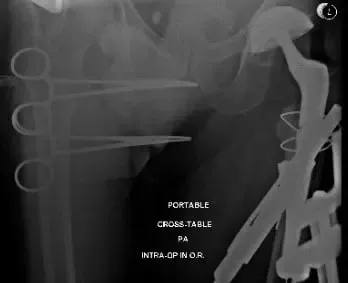

Imágenes de rayos X intraoperatorias y postoperatorias que muestran cables usados para la fijación de fracturas y el tallo femoral largo revisado.